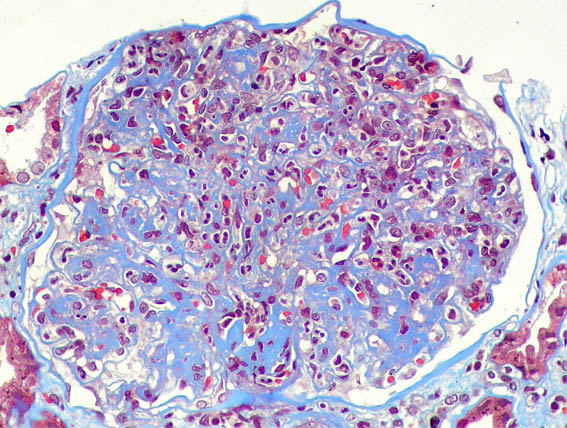

Figura 5.

Tricrómico de Masson, X400.